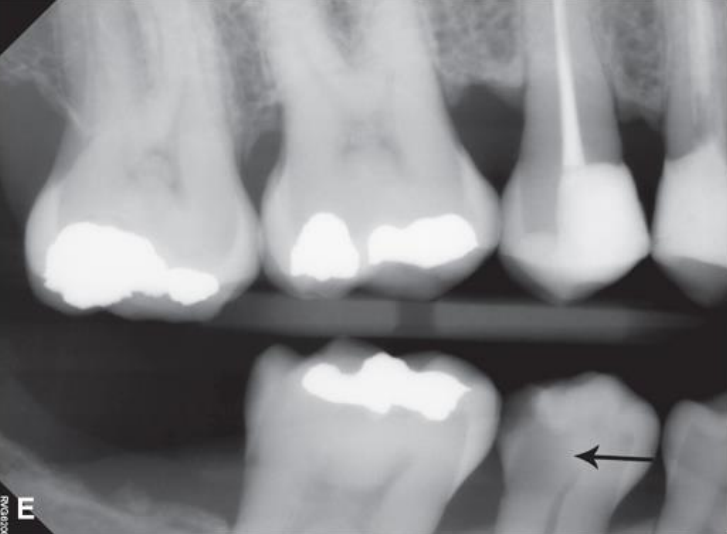

top arrow, classify this lesion based on the ADA caries classification system

D1

bottom arrow, classify this lesion based on the ADA caries classification system

D2